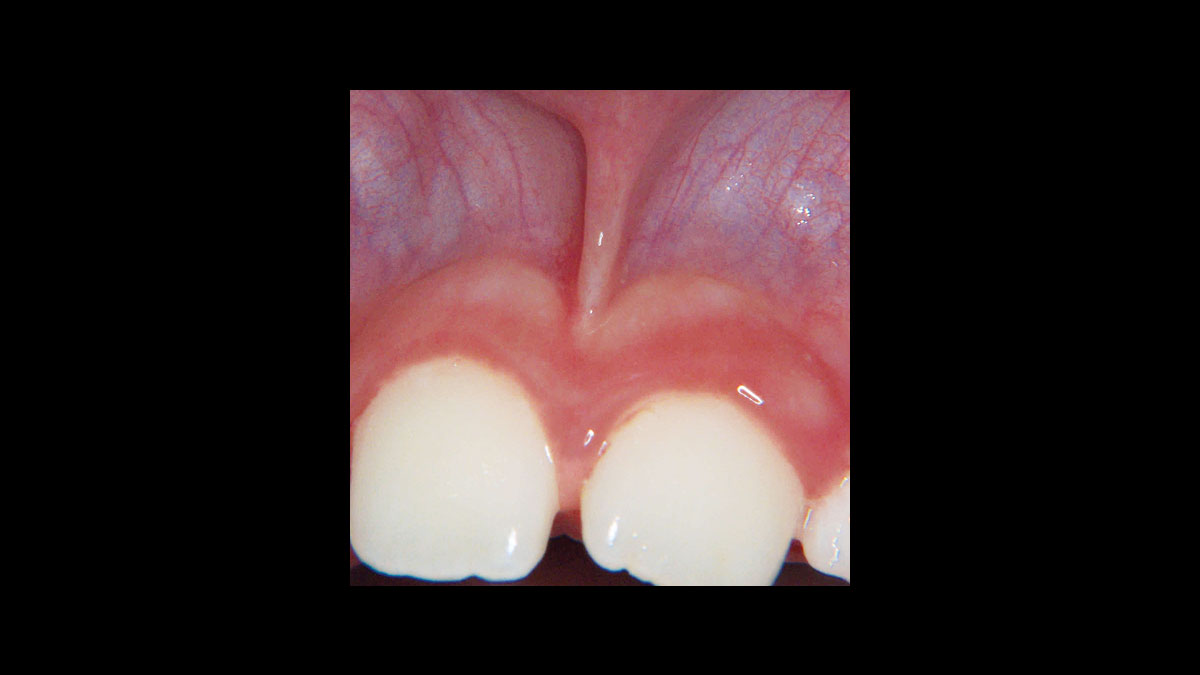

Frénectomie